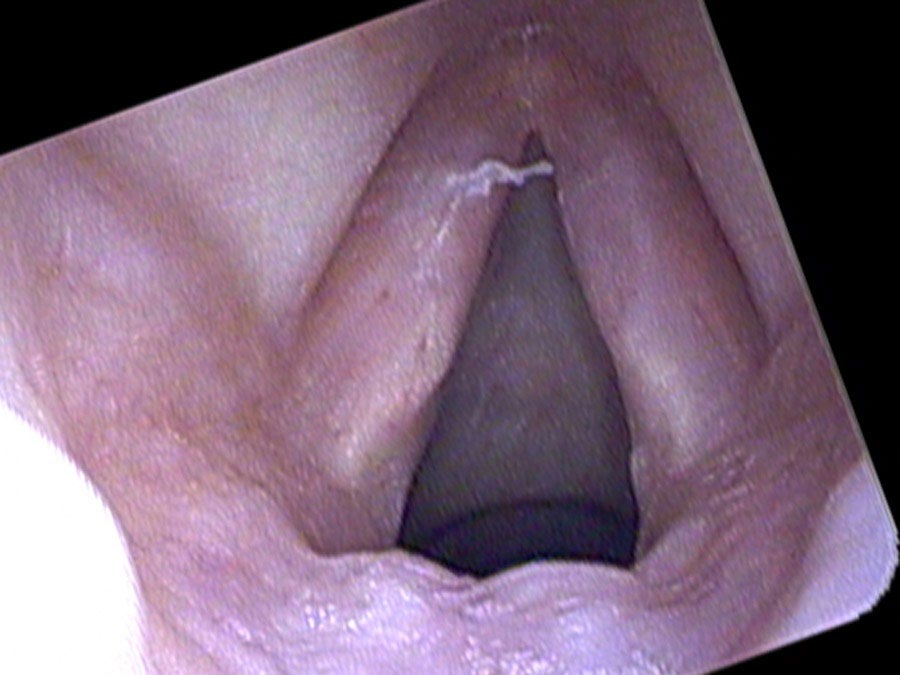

On endoscopy there are large polyps extending the length of both vocal cords, based on the superior surface and moving in and out with speaking and breathing. At times they get caught below her vocal cords and no sound comes out at all. Because they are so large, at times she squeezes her false vocal cords together and makes them vibrate. This combination produces her characteristically very deep, rough voice: up to three pitches generated simultaneously from the asymmetric true cords and the vibrating false cords.